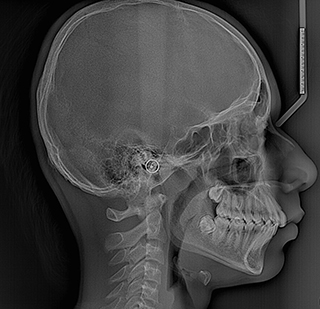

https://radiant3dxray.com/wp-content/uploads/2025/05/lateral-Ceph.jpg

Lateral Ceph

A Lateral Cephalogram is taken from the side of the face to assess and accurately measure the current and future relationship of upper and lower jaws and therefore assess the patient’s bite. This is particularly beneficial for orthodontic treatment planning.